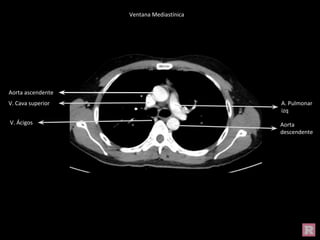

Aorta ascendente

Aorta

descendente

V. Cava superior A. Pulmonar

izq

V. Ácigos